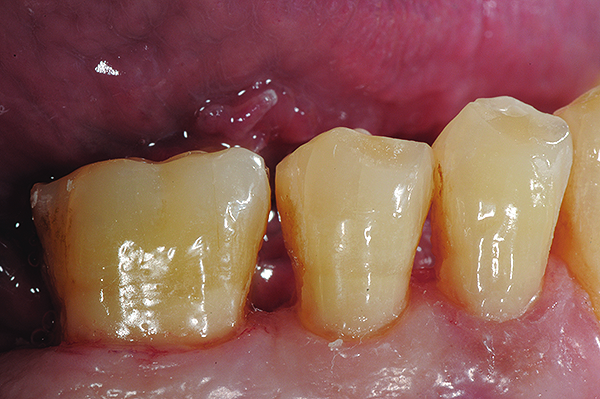

Non-carious cervical lesions (NCCLs), which are sometimes referred to as abfractions, are particularly challenging to restore and, therefore, are a good test of the restorative material or technique. Typically non-retentive, NCCLs have at least 50% of their margins in cervical dentin, and ineffective bonding will usually result in loss of the restoration. The etiology for these lesions remains controversial. Initially, it was believed that they were caused by vigorous or incorrect toothbrushing. However, based on the work of Grippo, most authorities now consider them to be caused by tensile and compressive forces created during tooth flexure, which disrupts the chemical bonds of the crystalline structure of enamel and dentin. This predisposes the area of flexure to cavitation.38

This type of lesion is often restored clinically with low-modulus composite resin. As discussed earlier, the portion of the restoration that is adhesively bonded to enamel typically produces an excellent seal and long-term bond, but the most cervical portions are often located in root dentin or cementum. This portion of the restoration is often found to have significant marginal staining or recurrent decay after only short periods of clinical service. On the other hand, GICs are not as sensitive to the tooth location because they bond to the mineral content of the tooth and are hydrophilic. They also have a low modulus, which seems ideal to resist cervical flexural forces.

The case demonstrated in Figure 6 through Figure 11 shows the ease with which non-carious Class V lesions can be handled with bulk-filled GIC restorations. Several cervical lesions (abfractions) of significant depth in permanent posterior teeth showed signs of turning carious (Figure 6). The author elected to restore them with the EQUIA technique. For non-carious lesions it is only necessary to freshen the cavity surface and margins with a diamond or carbide bur and to remove any visibly damaged hard tissue. It is then most ideal to remove any smear layer by treating the cavities with a weak acidic solution such as 20% polyacrylic acid (Figure 7). It is important that the clinician not substitute this acidic solution with a conventional phosphoric acid solution or gel used for etching tooth structure prior to resin bonding, as using the conventional solution will remove important mineral content that the GIC requires to bond with chemically. Once the cavities were isolated, a high-viscosity auto-curing GIC was mixed and syringed into the cleaned cavities with a bulk-fill technique (Figure 8). A plastic instrument was then used to condense and shape the material to the cavity walls and margins. The GIC will set in approximately 2:30 seconds to a sufficient level where it is safe to begin adjusting and finishing with rotary instruments. After the restorations were finished, they were coated with a nanofilled, light-cured resin glaze (Figure 9 and Figure 10). The glaze protects the surface of the GIC while it sets completely and enhances the physical strength of the final restoration. The completed GIC restorations (Figure 11) showed excellent esthetics comparable to composite resin.

Fig 6. In Case 2, pretreatment view of multiple non-carious cervical lesions.